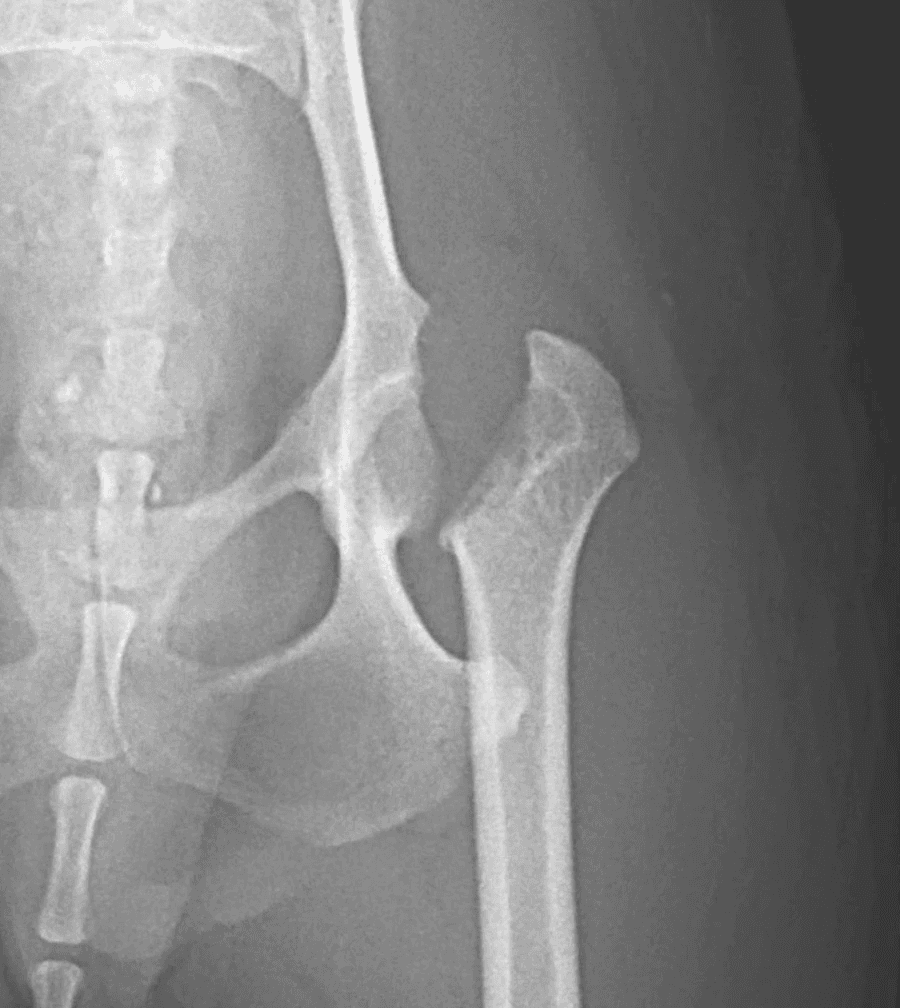

Avascular necrosis of the femoral head, also known as Legg-Calvé-Perthes disease in humans, is a condition in which the blood supply to the femoral head and neck becomes compromised. Without adequate blood flow, the bone tissue deteriorates (necrosis), leading to collapse and deformity of the femoral head. This process results in chronic pain and progressive loss of hip function.

The condition most commonly affects very young, small breed dogs. Early signs often include a mild but persistent hindlimb lameness that gradually worsens over time. In some cases, the lameness may become suddenly severe if a fracture develops within the femoral head or neck as the bone weakens.

Diagnosis is made with radiographs of the pelvis and hips that show the characteristic bone loss or deformity of the femoral head.

Both hips can be affected so it is important to assess both sides carefully

Surgical treatment is strongly recommended because the affected area causes pain and could potentially fracture. Healing is unlikely and painful femoral head will not heal or regain normal shape.